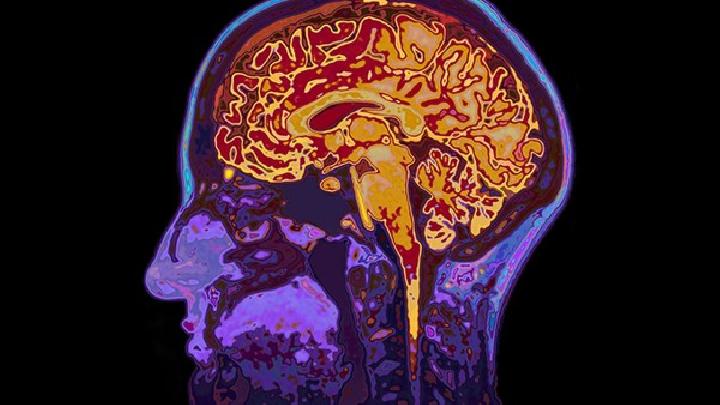

5.病人被送往医院后,除必要的治疗外,应先做头颅CT扫描,以便尽快明确诊断。脑疝患者应立即护送到医院进一步治疗神经外科。